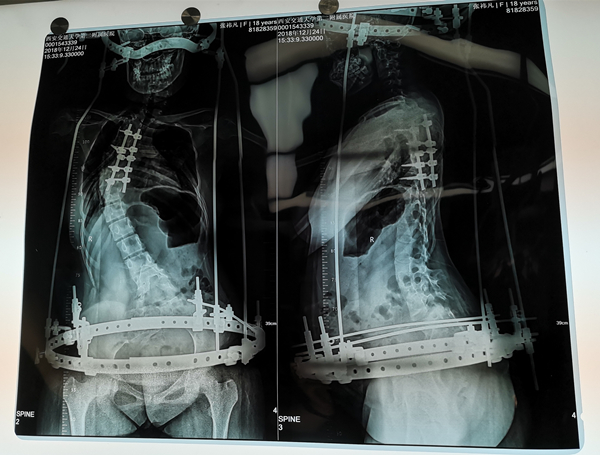

2019年1月15日,我院骨二科贺西京手术团队在麻醉手术科医护人员的大力协助下为一严重特殊脊椎侧弯患者成功实施了全脊柱截骨矫形钉棒固定术手术,术后患者畸形得到明显矫正,目前患者病情平稳正在康复中。

但是说话容易做事难,这个手术做起来还有比较大的风险,因为她之前的肺功能差,心功能也不强,胃肠的功能也差,脊柱的神经情况也有一些问题,几乎没有感觉到诱发电位运动,患者自己也觉得无力,牵拉着腿还有些疼,手术团队都想把这一系列症状一次解决,所以有潜在的巨大手术风险。明知山有虎,偏向虎山行,贺西京手术团队考虑到患者畸形明显,所以手术前准备也做得非常充分。1月15日在麻醉手术科医护人员的大力协助下,在全身麻醉下,贺西京教授为患者实施了全脊柱截骨矫形脊椎侧弯钉棒固定术,术中发现患者右侧多根肋骨成重叠挤压排列,脊柱畸形明显,手术难度可想而知,在手术医生、麻醉医生、手术室护士及神经功能监测人员的齐心协力下,经过几个小时的艰苦卓绝地作战,手术得以顺利结束,畸形得到明显矫正,目前患者病情平稳,说话都比以前有底气了,正在积极的康复中。